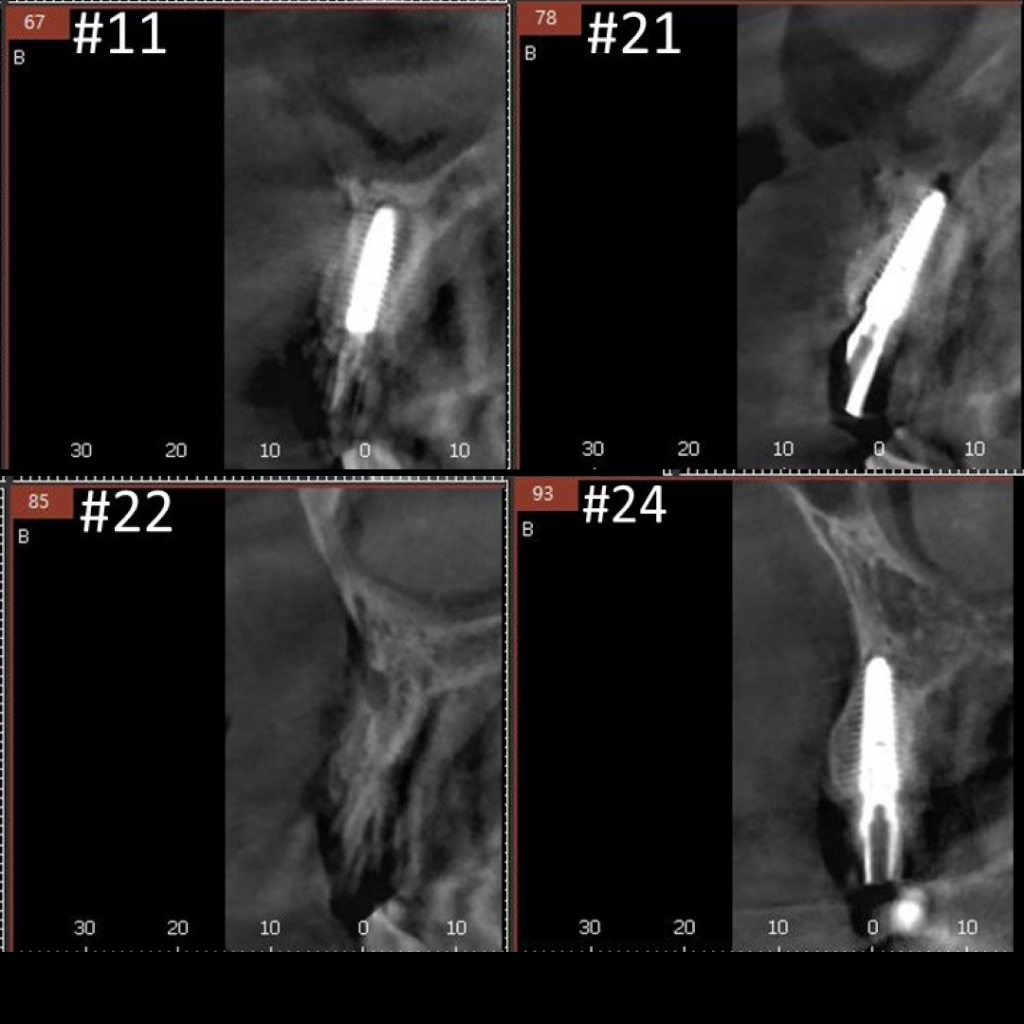

- Удаление несъемного мостовидного протеза по причине подвижности во фронтальной области верхней челюсти с диагнозом "Хронический генерализованный парадонтит и множественный кариес"

- Проведение имплантации AnyRidge с немедленной нагрузкой